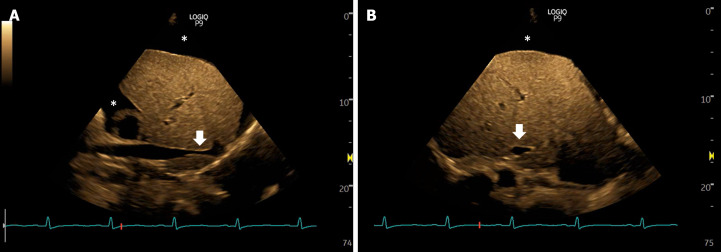

This article delves into the intricate challenges of acute kidney injury (AKI) in cirrhosis, a condition fraught with high morbidity and mortality. The complexities arise from distinguishing between various causes of AKI, particularly hemodynamic AKI, in cirrhotic patients, who experience hemodynamic changes due to portal hypertension. The term "hepatocardiorenal syndrome" is introduced to encapsulate the intricate interplay among the liver, heart, and kidneys. The narrative emphasizes the often-overlooked aspect of cardiac function in AKI assessments in cirrhosis, unveiling the prevalence of cirrhotic cardiomyopathy marked by impaired diastolic function. The conventional empiric approach involving volume expansion and vasopressors for hepatorenal syndrome is critically analyzed, highlighting potential risks and variable patient responses. We advocate for a nuanced algorithm for AKI evaluation in cirrhosis, prominently featuring point-of-care ultrasonography (POCUS). POCUS applications encompass assessing fluid tolerance, detecting venous congestion, and evaluating cardiac function.